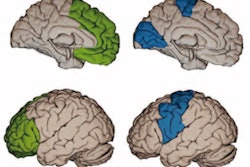

The investigators used the measures of baseline flortaucipir F-18/RO948 F-18 PET retention within a temporal region of interest, MRI-based Alzheimer's disease-signature cortical thickness, and amyloid PET centiloids -- along with models adjusted for age, sex, education, and cohort -- to predict changes in the MMSE. They assessed performance using R2 values, a statistic that describes how well a model fits the task.

Ossenkoppele and colleagues found that flortaucipir F-18 uptake predicted longitudinal changes in MMSE. This uptake effect was stronger than for Alzheimer's disease-signature cortical thickness and amyloid PET across all participants, including the amyloid-positive group with mild cognitive impairment and the amyloid-positive group who were not cognitively impaired.